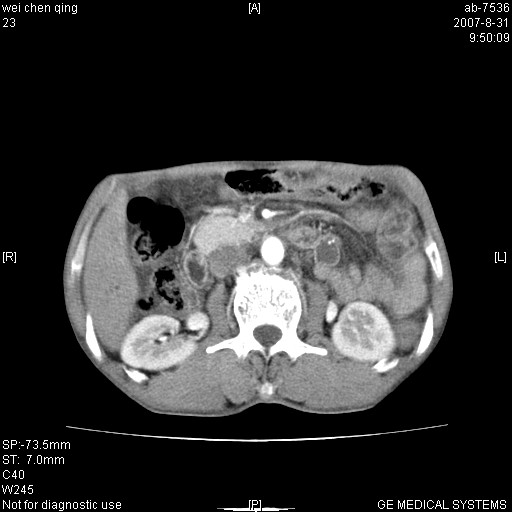

以下是引用zyyzzy在2007-8-31 14:34:00的发言:[br]该病人肝内胆管扩张,胆囊及胆总管未见明显扩张。在倒数第9层图像上可看到左右肝管结合部(肝总管)有软组织影,此处应薄层扫描。考虑肝总管占位(ca)、腹水。[br]